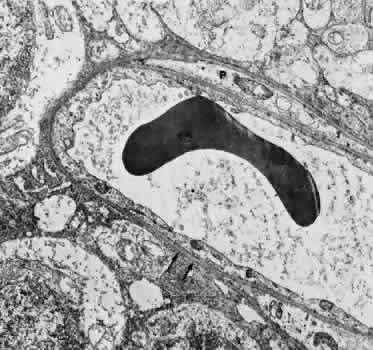

Retinal Veins and Venules Retinal veins are present in the inner retina, where they occasionally interdigitate with their associated arteries. When the two vessels cross, the artery usually lies anterior (toward the vitreous) to the vein.16 About one third of the time, however, the vein is anterior. At such crossing sites, the two vessels share a common adventitial coat.17 Under normal circumstances, the crossing vein's lumen may be decreased by as much as one third as a result of compression from the accompanying artery.17 There are many more arteriovenous crossings temporally than nasally, because the nasal vessels assume a much straighter course. Arteriovenous crossings are important because they represent the most common site of branch retinal vein obstructions. The separation of the superior and inferior halves of the perfusion of the retina is mirrored in the venous drainage pattern as well. Rarely does a retinal vein cross the horizontal raphe under normal circumstances. The retinal veins drain into the CRV, which also acts as the major efferent channel for the vessels of the optic nerve. Near the disc, the retinal veins are approximately 150 μm in diameter. Throughout the retina, the veins and venules generally follow the course of the arteries and arterioles. The intima of the veins consists of a layer of endothelial cells surrounded by a basement membrane continuous with that of the innermost layer of smooth muscle cells of the media. The media of the largest veins in the posterior retina consists of several layers of longitudinally oriented smooth muscle cells. The adventitia makes up the greatest part of the vessel wall and consists of loosely arranged collagen fibers and adventitial cells and is in direct contact with the glial cells of the retina. Venules are usually less than 20 μm in diameter.15 The media is composed of a single layer of cells resembling pericytes, containing poorly developed myofilaments and dense bodies. Elastin is not present. The adventitia contains little other than the basement membrane surrounding the pericyte (Fig. 5). Retinal Capillaries Throughout most of the posterior retina, the retinal capillaries are arranged anatomically in a dual layer. The superficial capillary layer is associated with the ganglion cell layer, whereas the deep capillary layer resides within the inner nuclear layer. Like capillary networks elsewhere in the body, the retinal capillaries assume a meshwork configuration to ensure adequate perfusion to all retinal cells. The deeper layer has a mesh diameter (i.e., the distance betweencapillaries) that characteristically averages 50 μm in diameter but varies between 15 and 130 μm. The more superficial layer has a slightly larger meshwork, on average 65 μm in diameter (16 to 150 μm). In the midequatorial and anterior zones, where the retina is thinner, only one capillary layer is present. In the fovea and the far retinal periphery, retinal capillaries are absent. The precise anatomical localization of the superficial layer of retinal capillaries appears to depend on the thickness of the accompanying ganglion cell layer.18 In the foveola itself and in the immediate parafoveal retina that contains a ganglion cell layer less than 15 μm thick, there are no superficial capillaries. This area represents the foveal avascular zone. Pathologic conditions that feature retinal capillary dropout, such as diabetes mellitus and sickle cell disease, may show an enlargement of this foveal avascular zone. Near the foveal margin, where the ganglion cell layer is of moderate thickness, the superficial retinal capillaries can be found in the outer aspect of the ganglion cell layer. In the intermediate parafoveal area, which has a ganglion cell region thicker than 45 μm, the superficial retinal capillaries are present within the ganglion cell layer itself. In the perifoveal region, where the ganglion cell layer is two to four cells thick, the superficial capillaries are found along the inner boundary of the ganglion cell layer, in contact with the nerve fiber layer. The major retinal vessels, especially the larger ones, usually are in contact with both the inner and outer boundaries of the ganglion cell layer. A capillary-free zone is present around each of the larger retinal arteries and veins (Fig. 6). It is more prominent around the arteries, measuring up to 100 μm. The capillary-free zone is a product of the embryologic vascular remodeling process. Direct diffusion of oxygen through the walls of the large retinal vessels probably initiates this process of vascular remodeling. Embryologically, numerous capillary-sized channels retract from the developing artery, leaving only a relatively few right-angled side-arm channels to serve as precapillary arterioles. In keeping these side channels to a minimum, the maintenance of an adequate pressure head for the remainder of the retina is ensured. In contrast, the radial peripapillary capillaries (RPCs) may develop in a different fashion, later than the other capillary beds, after vascular remodeling has already occurred.19 A distinct layer of capillaries, the RPC, is found adjacent to the optic disc, most prominently in the superior and inferior temporal aspects of the posterior pole (Fig. 7).20 These capillaries originate only from intraretinal arterioles and not from the optic disc vasculature. They are found within the inner aspect of the nerve fiber layer, making them the most superficial of all retinal capillaries. The RPCs tend to follow relatively long, straight paths, having few anastomoses with adjacent or underlying capillary beds. The RPCs do not traverse the central macular area. Their distribution suggests some anatomical correlation with various diseases. Cotton-wool spots are found in a distribution similar to the RPCs, and the arcuate scotoma seen in glaucoma appears to correspond to their pattern as well.21 The superficial peripapillary hemorrhages seen in glaucoma (Drance hemorrhages) may originate with the RPCs as well.22 Retinal capillaries range in diameter from 4 to6 μm. The capillaries throughout the retina, including those of the radial peripapillary network, have the same fine structure.23 The capillary wall consists of a continuous layer of flattened and longitudinally oriented endothelial cells and an incomplete layer of longitudinally oriented pericytes (Fig. 8). The pericytes (formerly referred to as mural cells) are closely spaced, resulting in an approximate ratio of pericytes to endothelial cells of 1:1, a relatively high ratio compared with elsewhere in the central nervous system. Ultrastructural examination of the endothelial cells of retinal capillaries shows that the cytoplasm of the cell bulges in the region of the nucleus. This area contains the Golgi apparatus, centrioles, and rough-surfaced endoplasmic reticulum. The remainder of the cytoplasm contains moderate amounts of smooth endoplasmic reticulum and mitochondria. The average endothelial cell thickness is 236 nm. Pinocytotic vesicles occur in the cells of the retinal capillaries. The vesicles are of uniform size, with an average diameter of 70 nm. Pinocytotic vesicles are found on the lumen (10% of total) and basement membrane (28%) side of the endothelial cells and free in the cytoplasm (62%). Approximately 2% of the volume of the endothelial cell is occupied by pinocytotic vesicles, a number that is substantially lower than that of other continuous capillaries. Pinocytotic vesicles of similar morphology and location are found in pericytes, but not in any number on glial cell membranes. Animal experimental evidence shows that these vesicles may be responsible for transporting substances from the vitreous cavity into the retinal vasculature in a unidirectional fashion.24 In the region of the endothelial cell junctions, cytoplasmic processes may overlap and form flap-like extensions that project into the lumen. The outer leaflets of adjacent endothelial membranes form very tight occluding junctions. The basement membrane surrounding the endothelial cell is well developed and continuous with the basement membrane surrounding the pericytes. The basement membrane of the retinal capillaries is structurally similar to that of the retinal arteries and veins in that collagen types 4 and 5, laminin, and heparin sulfate proteoglycan core protein are prominent features. Collagen types 1 and 2 appear to be lacking.12 Some areas show thinning of the basement membrane, and in these regions the endothelial cells and pericytes are closely apposed. Specifically, the capillary basement membrane between pericytes and endothelial cells is much thinner than the basement membrane covering the two types of cells.25 This arrangement probably allows increased communications between the cells. The retinal capillary basement membrane is thicker than in most other capillaries in the body, and in certain disease states such as diabetes, this thickness increases further.26 The pericytes of the retinal capillaries are not as elongated as the endothelial cells. They are endowed with multiple arm-like processes that wrap around the surrounding endothelial cells. Pericyte processes appear to cover about 85% of the entire circumference of the available capillary endothelial tube.25 Pinocytotic vesicles can be seen near the adventitial (outer) side of the cell body. In the peripheral retina, the retinal glial cells are in direct contact with the basement membrane surrounding the pericytes. Evidence suggests that the retinal pericytes are directly involved in the local control of retinal blood flow (RBF) and may affect endothelial proliferation as well.25 In diabetes there is an early, preferential loss of pericytes.27 Aldose reductase has been shown in the human pericyte, inviting speculation that abnormal accumulation of byproducts of this enzyme, such as polyol, may have a role in the selective pericyte loss.28 With aging there occurs a gradual loss of endothelial cells, followed by degeneration of the pericytes, an increase in capillary diameter, and a thickening and vacuolization of the capillary basement membrane surrounding the external surface of the pericyte.26,29 Age-related studies of larger retinal vessels show narrowing of the retinal arteries. This appears to be due to the fibrous replacement of contractile elements.17,30 These morphologic findings may account for the decrease in reactivity of the retinal arteries and arterioles to blood pressure and oxygen tension changes with age. A similar decrease in myogenic tone of the PCAs with age has also been demonstrated.31 OPTIC NERVE Most of the blood supply to the intraorbital portion of the optic nerve is through numerous perforating vessels from the pia mater. These pial vessels obtain their supply either directly from the ophthalmic artery or indirectly from recurrent branches back from the PCAs. There does not appear to be a “central artery of the optic nerve,” as once postulated.32,33 Axial branches off the CRA contribute to the circulation as well. The vascular supply of the optic nerve head was the source of considerable controversy in the past. The optic nerve head is situated at the watershed area between three separate circulations: the retinal, the posterior ciliary, and the pial (Fig. 9). Each of these systems contributes in part to the optic nerve head circulation. In some people, an incomplete arterial ring is formed within the sclera by the anastomoses of these three circulations. When present, it is referred to as the circle of Zinn-Haller. Most of the prelaminar blood flow is derived from the posterior ciliary circulation by way of the short PCAs.34,35 The prelaminar optic nerve may have separate tributaries from the short PCAs, or branches of these vessels may supply the optic nerve directly, as well as the choroid.36 There do not appear to be any direct anastomoses between the choriocapillaris and the capillaries of the optic nerve head, however. Neither are there major contributions from axial branches of the CRA. The circle of Zinn-Haller may contribute to the prelaminar circulation, but the pial arteries do not directly supply the prelaminar portion. They may anastomose with the prelaminar capillary network, however. The laminar portion of the optic nerve head is also supplied by the short PCAs, with variable contributions from the circle of Zinn-Haller.37 The CRA does not appear to contribute much to the supply of this area (Figs. 9 and 10).